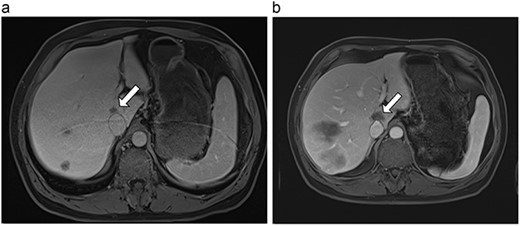

(a) Pre-ablation MRI demonstrates 6 mm lesion in caudate lobe of liver. (b) Post-ablation MRI (18 days postoperatively) demonstrates 40.4 mm complete ablation site in caudate lobe of liver.

| 1 (3a,b) | 61, F | Colon adenocarcinoma | 6-month FOLFOX | 1 | Laparoscopic microwave ablation | 6 | 40.4 | 34.4 | 10 | No |